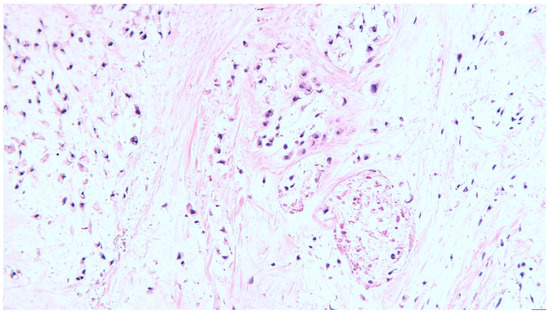

2. Clinical Case